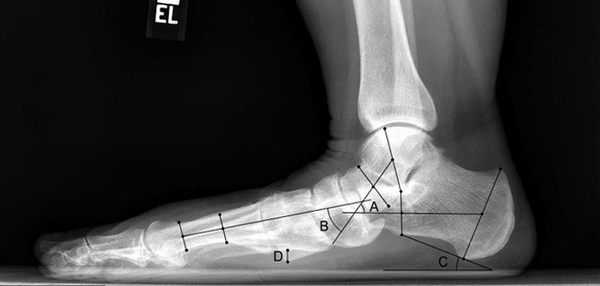

В ортопедии выделяют продольный и поперечный своды стопы. Первые располагаются вдоль ступни и поддерживаются мышечно-связочным аппаратом. Основную роль в укреплении этих сводов играет длинная подошвенная связка. Именно ее пластику чаще всего выполняют в случае развития продольного плоскостопия.

Поперечный свод стопы образован головками I-V плюсневых костей. В норме они образуют своеобразную арку. Поперечный свод поддерживается связками, сухожилиями и головкой мышцы, приводящей большой палец стопы. При нарушении мышечно-связочного баланса у человека возникает поперечное плоскостопие. Как правило, оно осложняется вальгусной деформацией I пальца стопы.

Рентген плоской стопы.